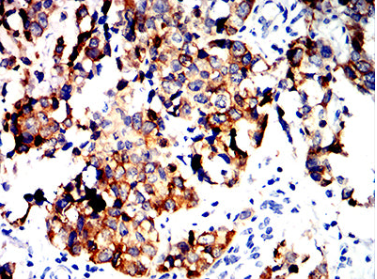

ALDH1L1 Mouse Monoclonal antibody[1B5E9]

The protein encoded by this gene catalyzes the conversion of 10-formyltetrahydrofolate, nicotinamide adenine dinucleotide phosphate (NADP+), and water to tetrahydrofolate, NADPH, and carbon dioxide. The encoded protein belongs to the aldehyde dehydrogenase family. Loss of function or expression of this gene is associated with decreased apoptosis, increased cell motility, and cancer progression. There is an antisense transcript that overlaps on the opposite strand with this gene locus. Alternative splicing results in multiple transcript variants.

Immunogen    Purified recombinant fragment of human ALDH1L1 (AA: 10-222) expressed in E. Coli.

IHC    1/200 - 1/1000